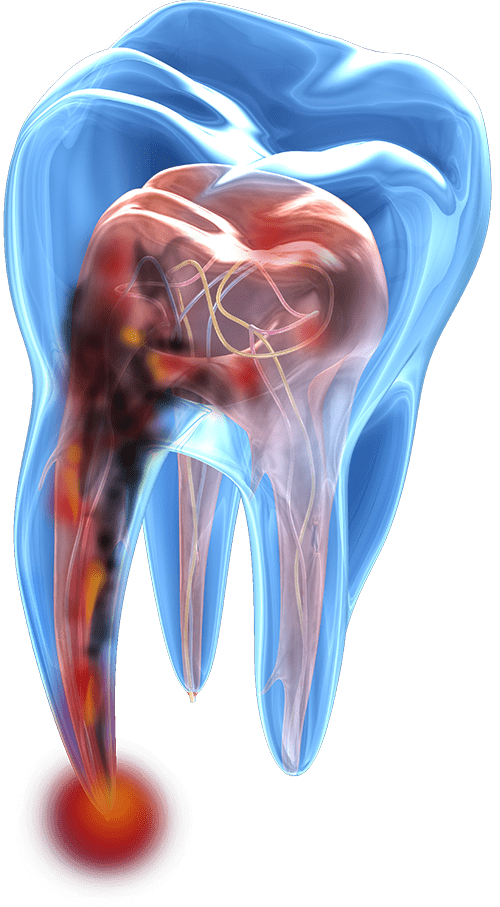

infected tooth model

A tooth root comprises the lower two-thirds of your tooth and serves as its anchor, maintaining the health of your jawbone. The radicular portion of the tooth, located below the pulp chamber, houses the root canal space. The apex, the tip of the tooth root, can be round, oval, long oval, flattened, or irregular. Incisors, canines, and premolars typically have a single root, while molars have two or three, each of which can become infected.

When pulp inside your tooth root becomes infected, it’s crucial to remove the pulp and bacteria to save your tooth, maintain good oral health, and overall well-being. During a root canal in South Elgin, IL, our oral surgeon begins by numbing the treatment site with a local anesthetic, ensuring you won’t feel any pain, although you may experience slight pressure during the procedure. Next, we drill a small hole in your tooth crown to access the pulp chamber. Carefully, we remove all the bacteria, infected pulp, and tissues. Then, we fill and seal the end of the tooth with a rubberlike material called gutta-percha. Finally, we restore the tooth with a crown or filling to protect it and restore its normal function. We accept various insurance plans and offer third-party financing options to ensure your treatment is both painless and affordable.